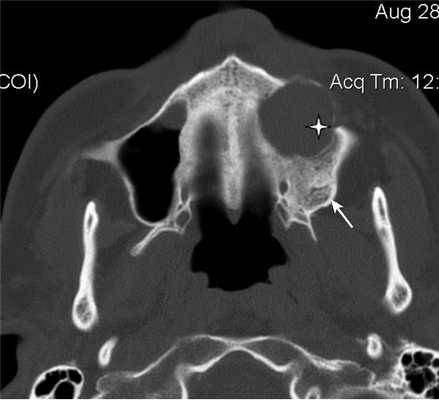

Рис. 3. Рентгеновская компьютерная томограмма околоносовых пазух. Аксиальная проекция, костное окно.

При воспалительных изменениях в ретроантральной жировой клетчатке верхнечелюстной пазухи на РКТ повышаются денситометрические значения ее плотности [10]. При одностороннем процессе отмечается выраженная асимметричность значений плотностей (рис. 4).